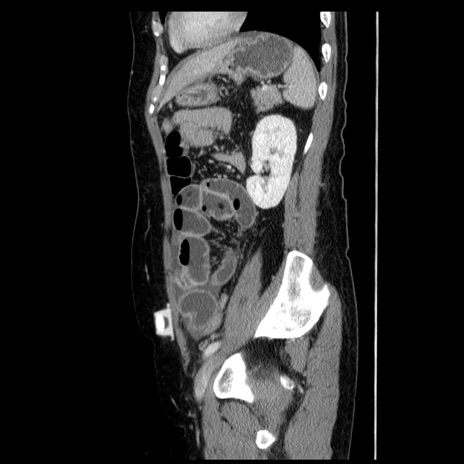

症例6(矢状断像)

【症例】50歳代女性

【主訴】下腹部痛

【既往歴】卵巣癌術後(8年前に当院で卵巣摘出)